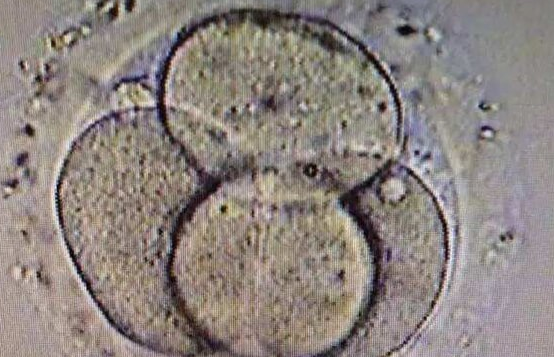

胚胎质量是决定移植成功与否的核心要素。即使通过促排卵获取了多个卵子,并成功培育出胚胎,但并非所有胚胎都具备发育成健康胎儿的潜力。一些胚胎可能存在染色体异常,这会导致它们在着床后无法正常发育,最终导致移植失败。例如,高龄女性的卵子更容易出现染色体问题,从而影响胚胎质量。